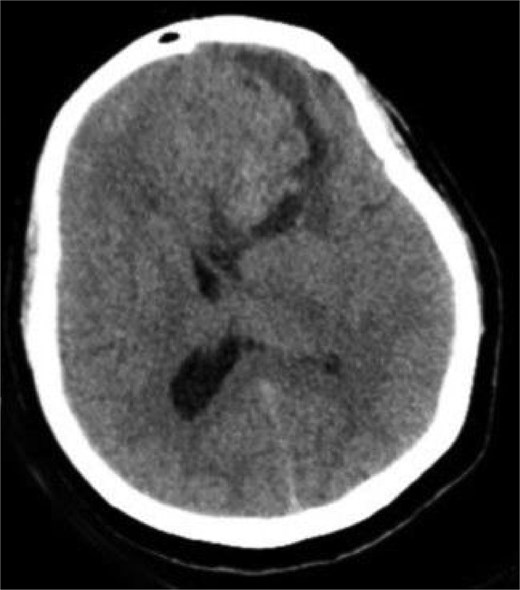

A 44-year-old right-handed woman presented with a two-month history of headache and blurred vision. Her medical history included hypertension and type 1 diabetes mellitus. She reported gradually worsening intermittent headache and bilateral visual blurring, more pronounced in the right eye. Symptoms exacerbated with physical exertion and were unrelieved by analgesics, leading to her referral. Examination revealed a conscious, alert patient with right eye proptosis. Visual acuity was 6/6 (left eye) and 6/9 (right eye). Fundoscopy identified bilateral Grade 3 papilledema. Non-contrast brain CT demonstrated a well-defined, isodense, dural-based extra-axial lesion in the left frontal region with a cystic component, measuring approximately 5.5 × 4.3 × 4.2 cm. It was associated with mild perilesional edema, mass effect, and a subtle contralateral falx shift. The initial impression was an atypical meningioma (Fig. 1). Subsequent MRI confirmed a large, falcine-based lesion that appeared isointense on T1- (Fig. 2) and T2-weighted images, demonstrating intense homogeneous enhancement post-contrast (Fig. 3). Signal voids suggested calcifications. The patient underwent gross total excision via a bilateral frontal craniotomy. The tumor was intradural and extra-axial, elevating the frontal lobe and was easily accessible; therefore, neither neuronavigation nor other intra-operative localization aids were utilized. Intraoperatively, the olfactory tract could not be clearly identified. A gap in the anterior cranial base was noted, but as there was no evidence of dural invasion or cerebrospinal fluid leak, no sealant was required. Gross examination of the resected specimen revealed a well-circumscribed, white nodule. Microscopically, sections showed benign spindle cell proliferation with alternating Antoni A and Antoni B areas (Fig. 4). Antoni A regions displayed nuclear palisading and Verocay bodies (Fig. 5), while Antoni B areas were edematous and myxoid (Fig. 6). No mitotic figures or atypia were seen. The definitive diagnosis was a benign olfactory groove schwannoma, notable given the initial radiological suspicion of meningioma. Her postoperative course was uneventful. A postoperative non-contrast CT brain obtained 48 hours after surgery confirmed gross total resection (Fig. 7). She was discharged with scheduled follow-up to monitor recovery and visual symptoms.

Preoperative CT brain without contrast (axial view) showing a well-circumscribed mass in the right frontal lobe resting on the falx cerebri, causing leftward midline shift with associated vasogenic edema and mass effect.